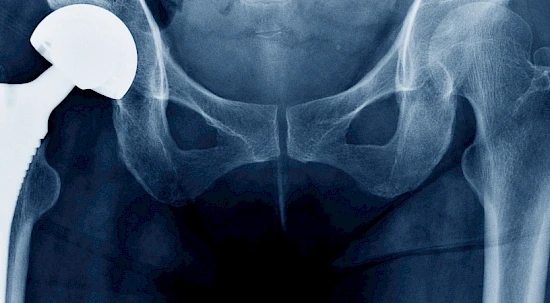

Partecipazione a Corsi di Perfezionamento sulla Chirurgia di Anca e Ginocchio

Aprile 2017 Berna – Direct Anterior Approach Instructional Course

Maggio 2010 Lucerna – Instructional Course Hip. Direct Anterior Approach